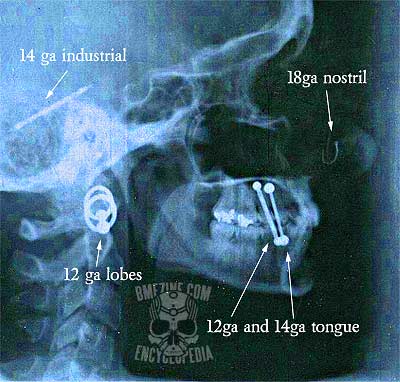

It is a common misconception by people in the medical community that body piercings will adversely affect the developing of an X-ray film. Jewelry will be visible on an X-ray film in the same way that a medical pin or metal plate is visible (generally showing up as bright white amongst the grayscale of the rest of the film). It will have no adverse effects on the patient, technician, or film.

That said, jewelry can obscure bone and tissues beneath it, thereby increasing the risk that an injury will go unnoticed if it is directly beneath the shadow of the jewelry.